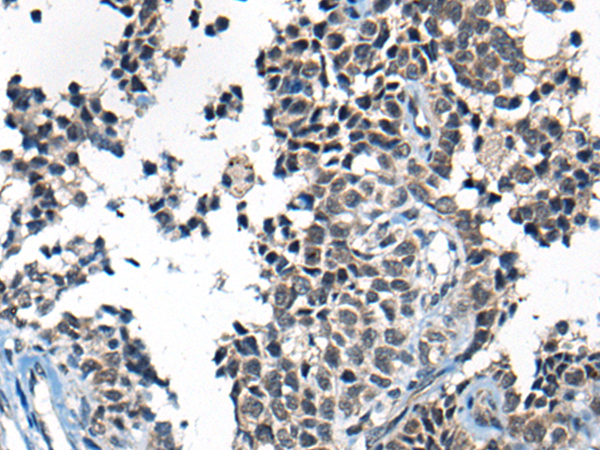

ELISA, IHC |

IHC positive control: |

Human ovarian cancer |

IHC Recommend dilution: |

25-100 |